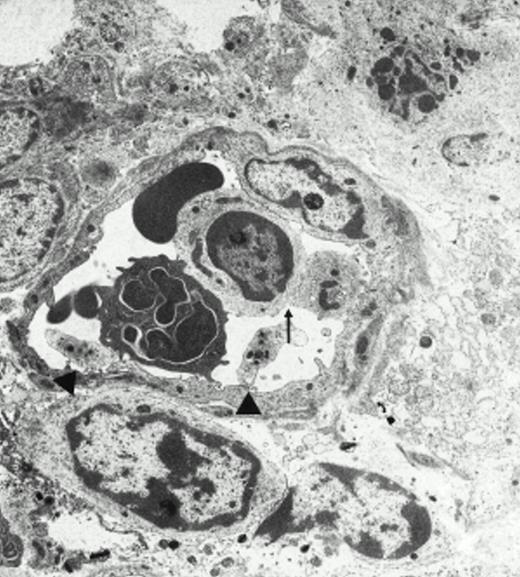

Electron microscopy.

Electron microscopy confirmed the presence of platelets adherent to endothelial cells in response to I/R. Platelets in various states of activation were frequently observed attached to the postischemic microvascular endothelium (Fig 3). Adherent, single, or aggregated platelets appeared degranulated extending pseudopodia to the endothelial cell surfaces. In most instances, platelets adhered directly to endothelial cells, and obvious endothelial denudation was not detected. Occasionally, neutrophils carrying activated platelets adherent on the surface could be demonstrated (Fig 3). In animals not exposed to I/R, few platelets with direct contact with the endothelium were seen. Platelets in these animals generally retained a discoid shape with prominent α-granules.

Platelets in postischemic microvasculature visualized by electron microscopy. Electron microscopy demonstrated platelets attached to both endothelial cells (arrowhead) and neutrophils (arrows) in response to I/R (upper panel, original magnification × 3,000). Platelets bind directly to endothelial cells (lower panel, original magnification × 20,000).